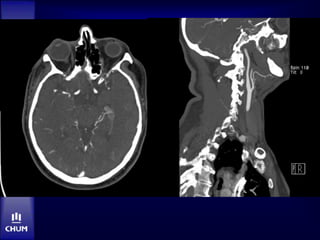

CT: 18 hres

CTA: 18 hres

M. A.

 24 hres post-tPA

• Deterioration subite

• NIHSS 23

CTA: 24 hres

IA = echec